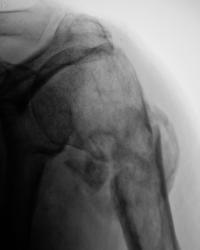

Пациент направлен в рентгеновский кабинет для рентгенографии плечевого сустава. Травма. Произведена рентгенография в прямой проекции.

3.Perelom.1..jpg

После наложения гипсовой повязки, хирургами пациент на контроль направлен не был.

После снятия гипсовой повязки, пациент направлен на "рентген-контроль" для анализа процесса консолидации.

картина посттравматического остеомиелита.

Я не уверен, что есть признаки остеомиелита, скорее можно предположить резорбцию костной ткани в месте перелома в счетании с формированием костной мозоли.Важна клиника (при остеомиелите следут ожидать гипертермию). Сколько прошло времени между сериями снимков?

1,5 месяца.

Учитывая наличие хорошо выраженной мозоли может и зарастет, но не очень нравится местоположение отломка медиально, вероятно с ним будут "проблемы".

О консолидации говорить нельзя.